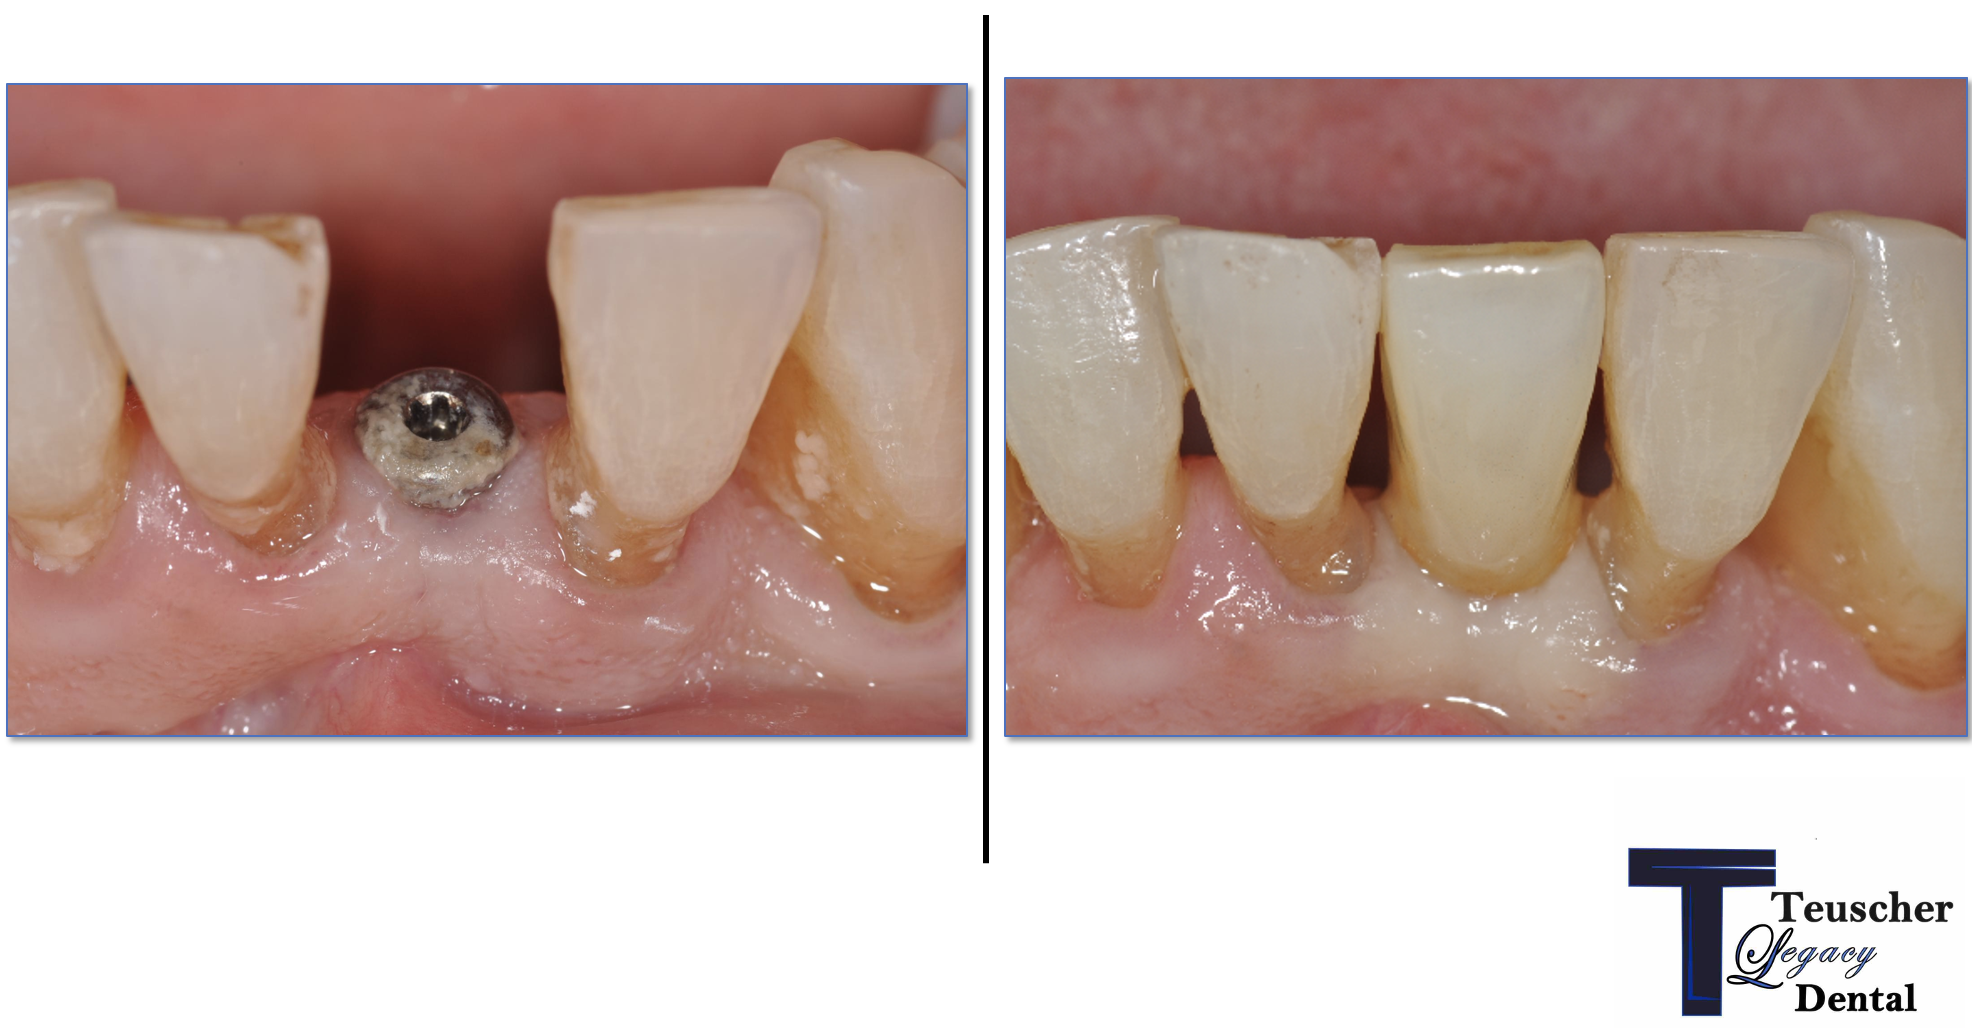

📸 Section 5: Real Case Example (Before/After Photos)

Here’s a case where Dr Brayden Teuscher extracted a molar tooth and placed a bone graft. We detailed this case further in this blog post.

🧪 Step 3: Bone Graft and Collagen Plug

To prevent bone collapse, we placed a biocompatible bone graft into the socket.

The material acts as a scaffold that your body gradually replaces with living bone. Usually these bone grafts are from human cadavers, (allograft) but can also be from your own body (autograft), cows or horses (xenograft), or completely synthetic (alloplast).

In our case, we used a cadaver bone particle mix to fill the socket. A collagen plug and PTFE non-resorbable sutures were added to stabilize the area and protect the graft during healing.

Images:

A clear picture of the collagen plug over the top of the bone graft. You can see two of the white sutures as well.

After the bone graft. Notice where the roots used to be, the socket appears filled with bone particulate.

✅ Goal: preserve ridge volume, gum contour, and future implant site quality.